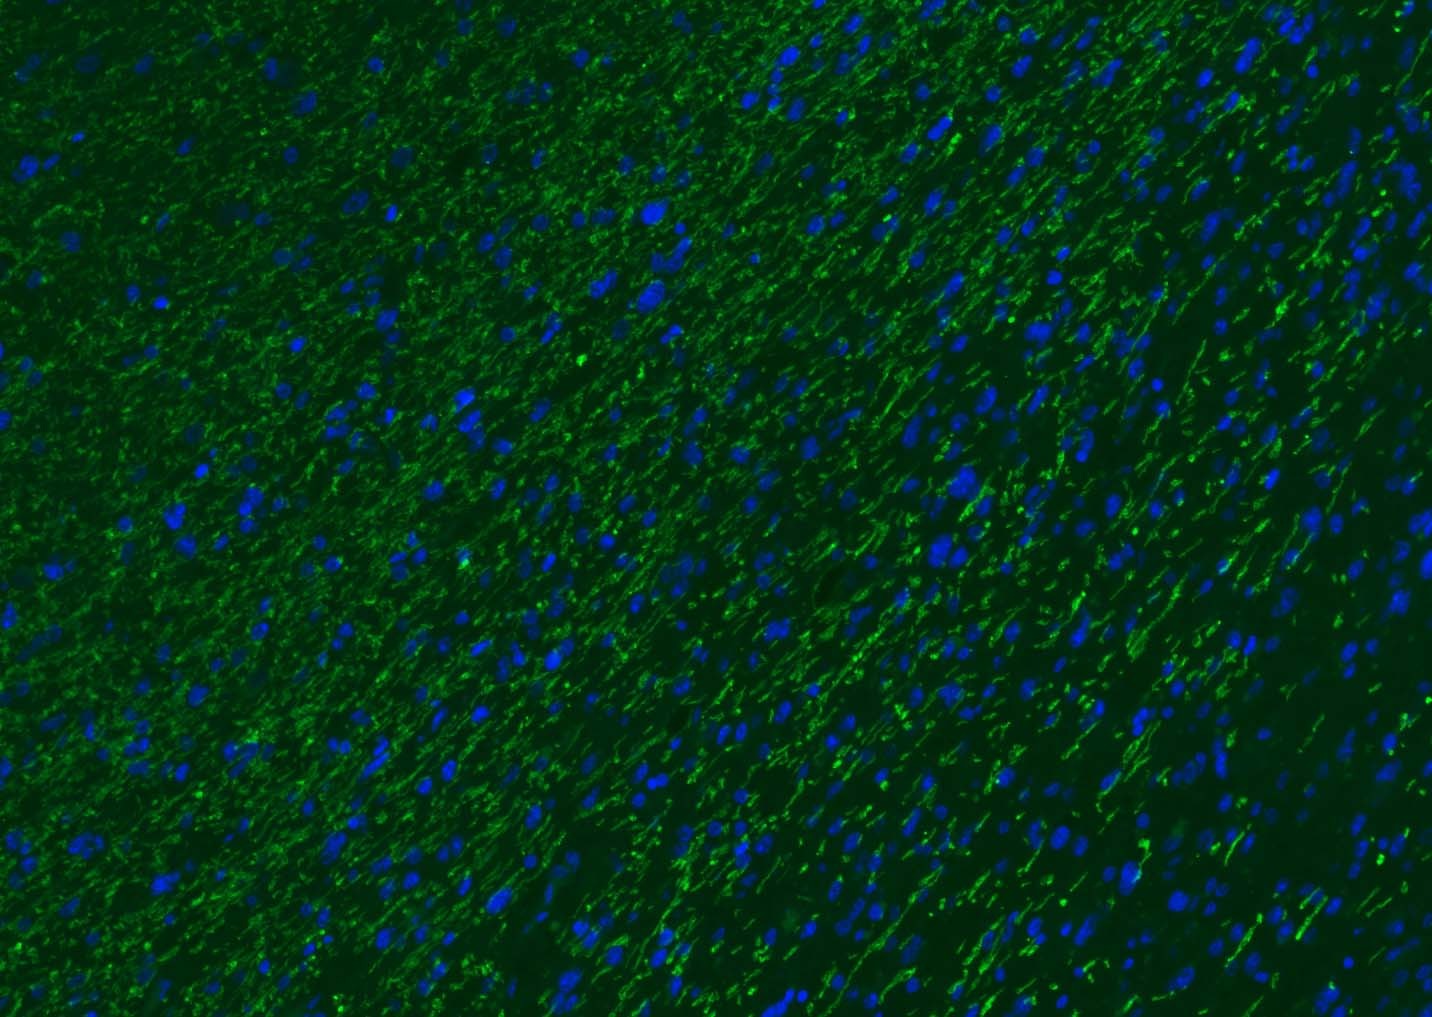

2. Paraformaldehyde-fixed, paraffin embedded (rat brain); Antigen retrieval by boiling in sodium citrate buffer (pH6.0) for 15 min; Blocking buffer (normal goat serum) at 37°C for 30 min; Antibody incubation with (MBP) Polyclonal Antibody, Unconjugated (TMAB-01110) at 1:200 overnight at 4°C, followed by a conjugated Goat Anti-Rabbit IgG antibody for 90 minutes, and DAPI for nucleus staining.

3. Paraformaldehyde-fixed, paraffin embedded (human brain); Antigen retrieval by boiling in sodium citrate buffer (pH6.0) for 15 min; Blocking buffer (normal goat serum) at 37°C for 30 min; Antibody incubation with (MBP) Polyclonal Antibody, Unconjugated (TMAB-01110) at 1:200 overnight at 4°C, followed by a conjugated Goat Anti-Rabbit IgG antibody for 90 minutes, and DAPI for nucleus staining.